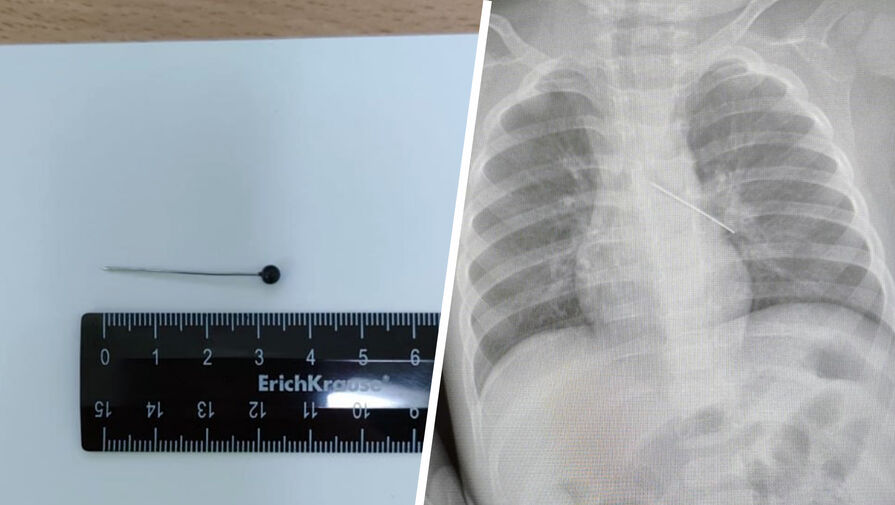

Врачи Центра охраны материнства и детства спасли 17-месячного ребенка, который из любопытства проглотил булавку. Об этом сообщила президент медицинского учреждения Лариса Белоцерковцева в Telegram-канале.

По словам медика, мать мальчика вовремя заметила беду и привезла ребенка в медицинское учреждение. Обследование показало, что инородный предмет зафиксировался в бронхах.

«Если бы бригада наших высокопрофессиональных специалистов не смогла удалить инородный предмет с помощью бронхоскопа, ребенка пришлось бы передавать торакальным хирургам для проведения большой операции», — пояснила Белоцерковцева.